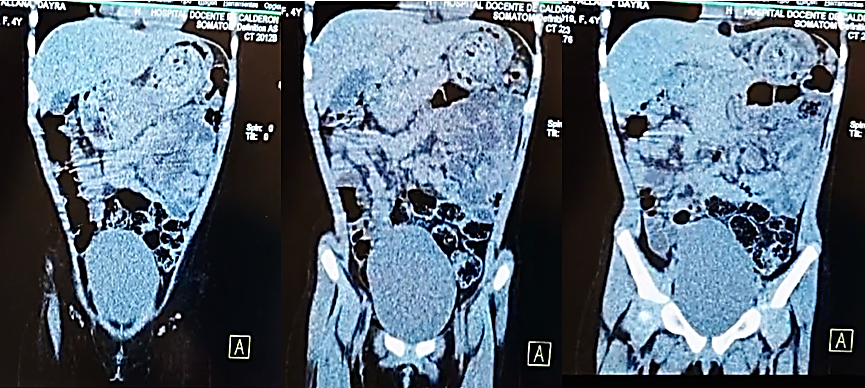

Se procede de forma inmediata a solicitar tomografía computarizada simple de Abdomen para confirmar diagnóstico de tricobezoar. Se evidencia masa a nivel de epigastrio. (figura 1)

Figura 1. Tomografía de Abdomen

Reporte: cortes coronales, cámara gástrica distendida con engrosamiento de las paredes y contenido heterogéneo en su interior, engrosamiento de las paredes antroduonenal, región antral y primera porción del duodeno, distención leve de asas intestinales (intestino delgado).

Concluye: contenido heterogéneo en cavidad gástrica sugestivo de Tricobezoar.